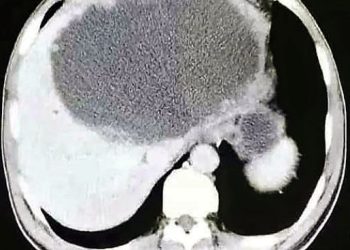

ভুল খাদ্যাভাসের মাসুল! মাংসাশী পরজীবী খেয়ে ফেলছে শরীরের এই অঙ্গ

চিনাদের খাদ্য তালিকা নিয়ে মানুষের আলোচনার শেষ নেই। পোকামাকড় থেকে শুরু করে অন্যান্য প্রাণীর মাংস। কোনোটাই বাদ নেই তাদের খাবার ...